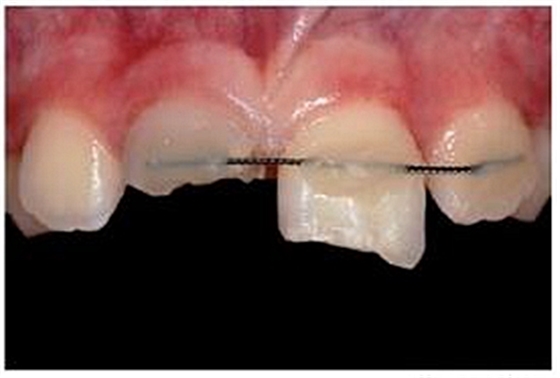

一位九歲男孩在騎車時不慎摔倒而導(dǎo)致牙齒外傷。受傷后立即進(jìn)行了應(yīng)急處理,首先對折裂的中切牙進(jìn)行牙髓治療、并對松動脫位的左側(cè)中切牙進(jìn)行活動夾板固定(21)。受傷后兩周,患者前來就診,要求行兩側(cè)上中切牙的后續(xù)治療,并咨詢能否及如何修復(fù)右側(cè)斷裂的中切牙(11)。

專業(yè)醫(yī)師對患者進(jìn)行了仔細(xì)檢查及診斷分析。11被診斷為冠根折伴牙髓暴露及大面積牙體缺損。21被診斷為側(cè)向移位伴冠折。檢查活動夾板在位,兩中切牙根管治療術(shù)中,氫氧化鈣根管內(nèi)封藥。11明顯變色。11用Cavit暫封,21復(fù)合樹脂充填。11腭側(cè)頸部有一折裂片。